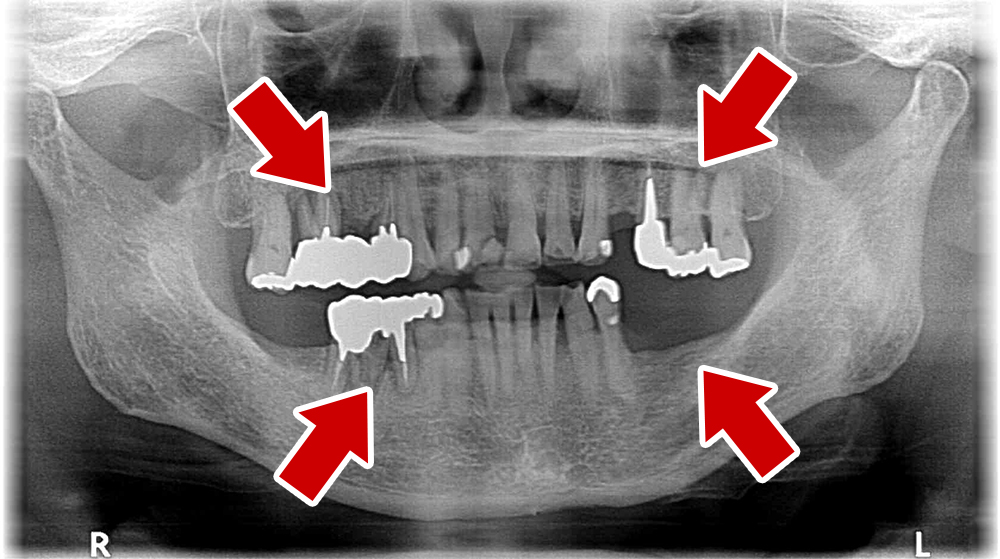

64歳 女性 紹介患者様

- 主訴

- 上下左右の歯が無くて、食べずらい、右下の歯が痛い

- 処置内容

- 右上3本、左上1本、右下3本、左下3本、鎮静麻酔

- 治療費用

- 上顎:約180万円(税込)下顎:約170万円(税込)

- 治療期間

- 上顎:約9か月、下顎:約6か月

- リスク

-

術後の腫れ、痛み(ピークは3日後、1週間で軽減)

上部構造物、仮歯の破折、人工歯根脱落リスクがあります